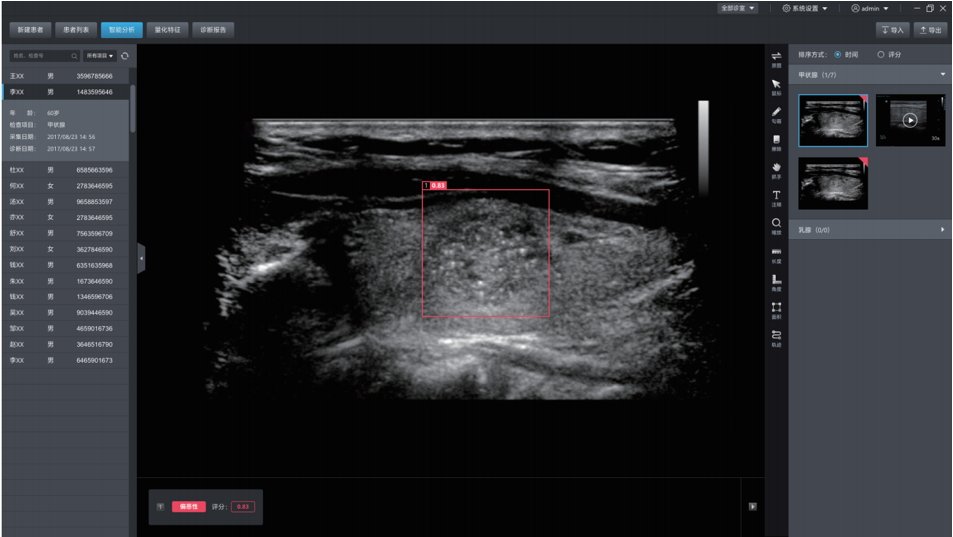

DEMETICS 超声诊断机器人

德尚韵兴医疗科技采用自主研发的深度学习框架DE-Light, 在专家标注的大量样本基础上,研发的超声辅助诊断系统,可自动探测超声图像中的病灶,并自动判断良恶性。甲状腺结节良恶性的准确率达到85%,达到三甲医院主治医生的水平。